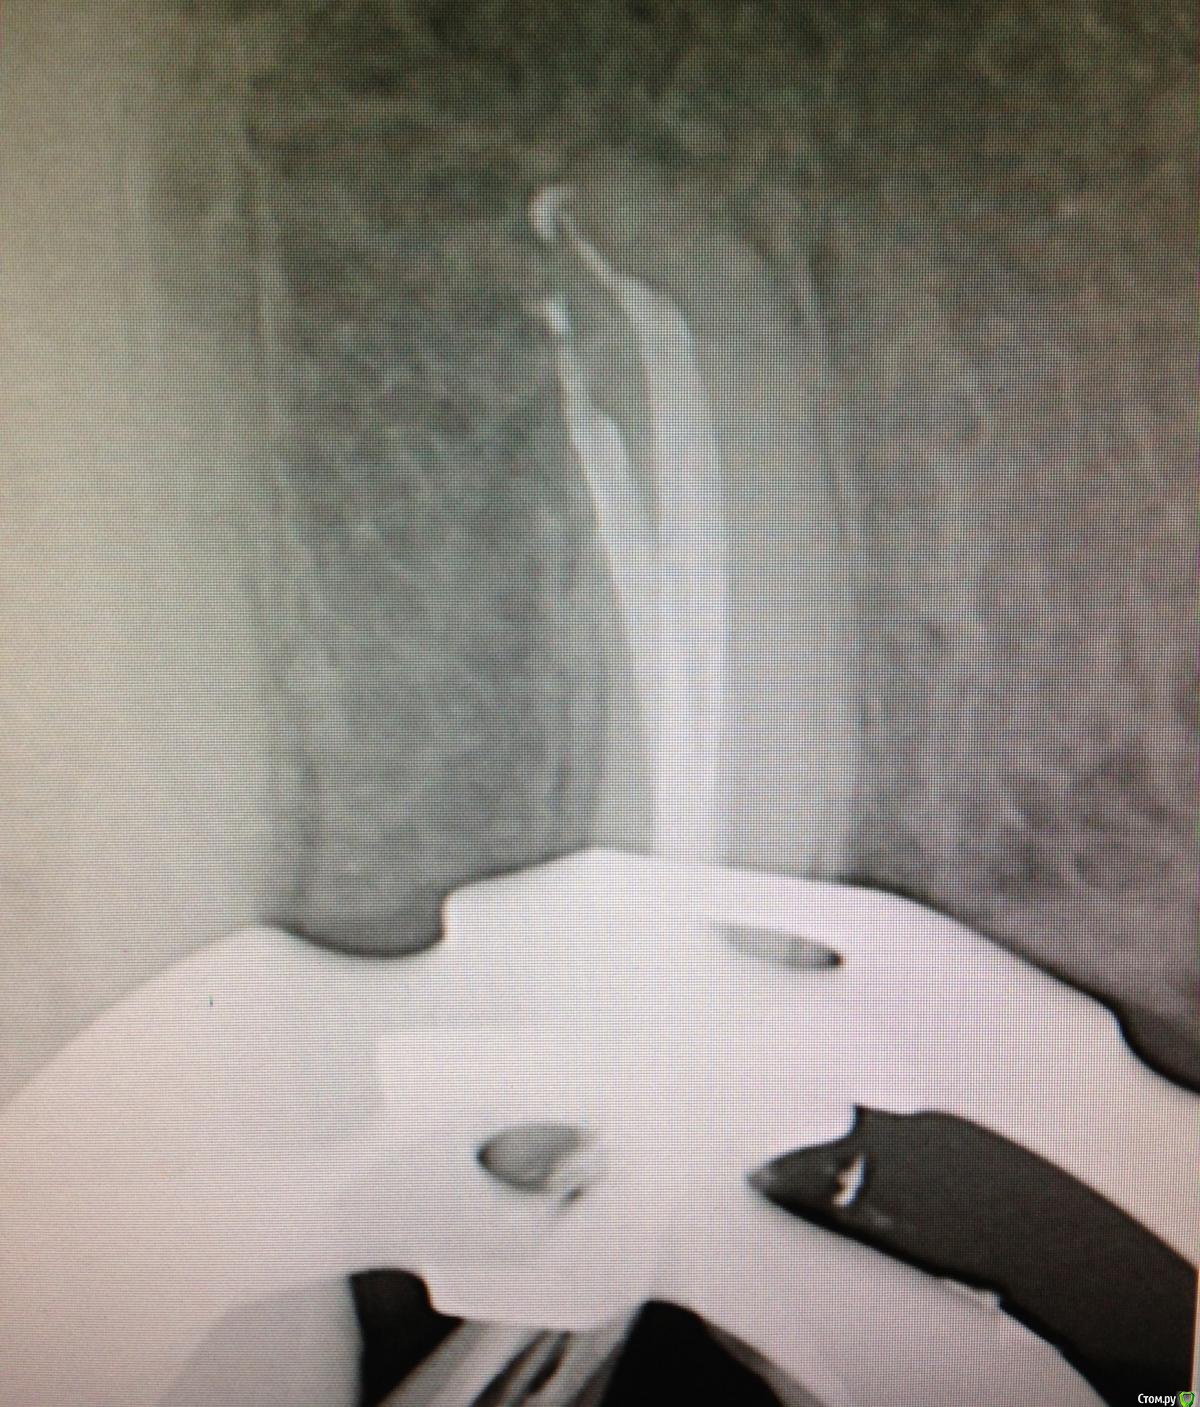

SSTi Опубликовано 7 января, 2015 Автор Поделиться Опубликовано 7 января, 2015 21 запаковал. 4 Ссылка на комментарий